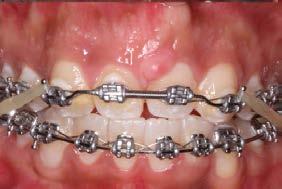

En su análisis facial la paciente presentó un perfil convexo con un tercio inferior aumentado, patrón dolicocefálico severo de VERT, sonrisa gingival e incompetencia labial (Figura 1 A). Durante la exploración intraoral encontramos mordida abierta anterior con apiñamiento severo superior (-13mm) e inferior (-11.5mm), líneas medias desviadas y no coincidentes con la línea media facial, el diente 11

mutilado y con tratamiento de conducto inconcluso, overbite -3mm y overjet 8mm (Figura 1 B).

La paciente fue tratada con aparatología fija MBT slot 0.022”, se utilizaron bandas en primeros molares superiores e inferiores y tubos en segundos molares superiores, se realizaron extracciones de los dientes 11, 21, 34 y 44. Se colocaron los brackets de centrales en laterales, los de laterales en caninos y los de caninos en premolares.

En la fase de alineación se utilizó una secuencia de arcos comenzando con el arco 0.012” NiTi, 0.014” NiTi y 0.016” Niti. Se realizó la tracción del diente 21 y se mantuvo en boca hasta comenzar la fase de trabajo, posteriormente se realizó la extracción (Figura 3).

Durante la fase de trabajo se realizaron sets de intrusión y utilización de close coil; una vez cerrado el espacio entre los incisivos laterales, se indicó el uso de elásticos de clase III 3/16 4.5 oz para corregir la mordida borde a borde (Figura 4).